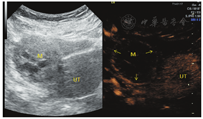

患者女,34岁,于顺产后43 d检查发现右侧卵巢囊实性肿块入院治疗。既往体健,生育史:孕4产2,曾流产2次。妇科查体:子宫正常大小,活动可,于右侧附件区可扪及一直径约5 cm肿块,活动可,界清,无明显压痛,左侧附件区未扪及明显肿块。辅助检查:CEA、CA199、CA125、AFP、卵巢癌相关抗原均为阴性。经阴道超声示:子宫体积正常(三径和约142 mm,宫颈厚28 mm,内膜厚约5.0 mm),宫壁未见明显肿块占位;右侧卵巢体积大、内可见一大小约49 mm×41 mm×39 mm的囊实性肿块,肿块边界清楚,形态规则,内部回声不均匀,可见多个囊性无回声区(较大者约13 mm×11 mm)(图1),能量多普勒示肿块内部及周边可见点条状血流信号(图2),脉冲多普勒(PW)示最高流速(Vmax)0.18 m/s,最低流速(Vmin)0.09 m/s,阻力指数(RI)0.50;子宫及左侧附件区未见明显异常回声。超声提示:①右侧卵巢内囊实性肿块;②子宫及左侧卵巢未见明显异常。进一步行超声造影成像示:增强早期时,右侧卵巢内肿块周边呈环状高增强,并早于子宫肌层增强(图3);内部实性部分呈不均匀等增强,并与子宫肌层同步增强;内部囊性部分无增强(图4)。造影剂消退时,肿块内部早于子宫肌层消退,而周边仍呈环状增强(图5),超声造影提示右卵巢肿块血供较丰富,表现"快进快退"。磁共振增强扫描提示:子宫右上方占位,考虑来源右卵巢性索间质肿瘤-颗粒细胞瘤可能,其他待排。术前拟诊"盆腔肿块性质待查",予行腹腔镜下右侧附件切除术,术中所见:右侧卵巢内见一肿瘤,直径约5 cm,呈囊实性,表面包膜完整,右侧输卵管攀附其上,外观正常;子宫正常大小,左侧卵巢及输卵管外观正常。术后病理镜下见肿瘤细胞弥漫性增生,呈片状、条索状,灶性腺样结构,部分区域可见大小不等的囊腔,核大小较一致,圆形或椭圆形,核仁可见,核分裂象约1~2个/10HPF,间质纤维组织及厚壁血管增生,黏液样变、灶性出血。免疫组化结果显示:Vimentin(+),CD10(+),ER(-),PR(-),CD34(血管+),EMA(-),P53(散在弱+),Ki67(灶性15%+)(图6)。结合免疫组化考虑卵巢性索-间质肿瘤,倾向卵巢间质瘤,送至复旦大学妇产医院会诊,诊断为右侧卵巢微囊性间质瘤。

卵巢MCST形态学表现上有完整的包膜,且实性肿块内部有特征性的微囊结构,这些在二维超声图像上有相应的表现,如本例患者卵巢MCST经阴道超声表现为卵巢内囊实性肿块,肿块边缘可见少量正常卵巢组织并与卵巢界线清楚,肿块边界清楚,形态规则,中央部可见多个规则的囊性无回声区(长径约10 mm)、透声好。彩色血流示肿块周边可见半环形血流信号,内部可见少许点状血流信号显示,频谱多谱勒显示为中等阻力。超声造影增强早期表现为包膜最先呈环状高增强(始增时间早于宫体),内部与宫体同步等增强,并由周围向中心增强,消退期表现为内部早于子宫肌层消退,而包膜仍呈环状持续高增强。